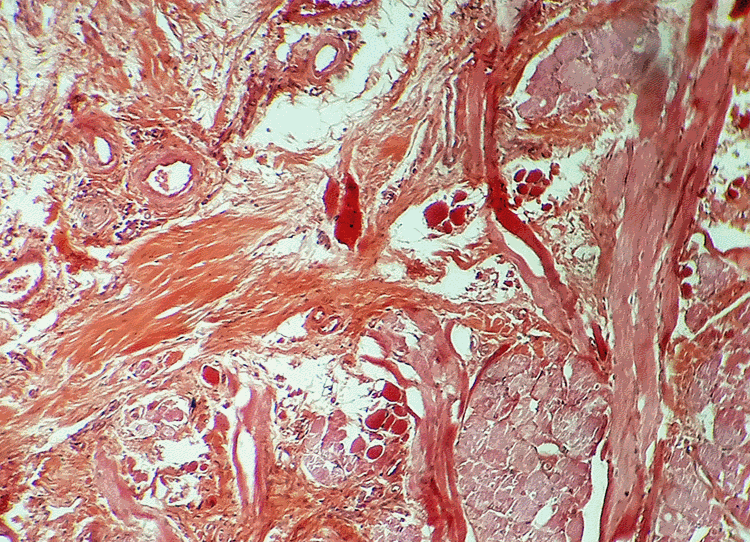

Aujourd'hui, le coffret renferme une collection de coupes histologiques réalisées en 1926 à l'Hôpital Saint Michel à Paris. Nous avons photographié quelques-unes de ces lames portant les fines tranches de tissus biologiques humains préparées à partir de prélèvements sur des patients. Nous ne sommes pas à même de reconnaître les zones médicalement intéressantes et, pour les photographies, nous avons privilégié le jeu des formes et des couleurs : c'est une façon de remarquer la qualité des préparations presque centenaires. Le microscope que nous avons utilisé est plus actuel que l'élégant "Nachet à pied anglais" recommandé, autrefois, pour les travaux d'histologie et de bactériologie. |

| Doigt (Dr J. Récamier - 1926) | Sein (Dr V. Pauchet - 1926) | ||||||||||||||||||||||||||||||||||||||||||||||||||||||||||||||||||||||||||||||||||||||||||||||||||||||||||||||||||||||||||||||||||||||||||||||||||||||||||||||||||||||||||||||||||||||||||||||||||||||||||||||||||||||||||||||||||||||||||||||||||||||||||||||||||||||||||||||||||||||||||||||||||||||||||||||||||||||||||||||||||||||||||||||||

Ces images, qui correspondent à des zones différentes d'une même coupe histologique de doigt, montrent la complexité de la structure des tissus biologiques... |